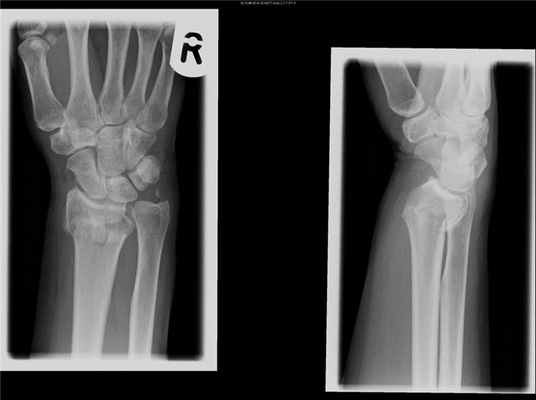

Наиболее частый вид перелома среди костей предплечья — это перелом лучевой кости в «типичном месте», который распространен среди пожилых женщин.

• лучевой кости в типичном месте возникает вследствие падения на прямую руку с упором на ладонь. Немного реже такого рода перелом возникает при падении на тыльную часть ладони. Более распространены такие переломы среди людей, страдающих заболеваниями костей, снижающими их плотность. В большинстве случаев кость ломается на пару сантиметров выше лучезапястного сустава;

Переломы костей предплечья проявляются резкой болью в месте травмы, отеком, болезненностью при пальпации, крепитацией отломков. При переломе проксимального отдела костей предплечья возникает ограничение движений в локтевом суставе, при переломе дистального отдела костей предплечья — в лучезапястном суставе. При переломе обеих костей предплечья в средней трети возникает видимая деформация и укорочение предплечья. Переломы дистального метаэпифиза лучевой кости часто называют переломами «в типичном месте». Такие переломы чаще встречаются у женщин пожилого и старческого возраста на фоне остеопороза и возникают при падении на вытянутую руку.

При переломах лучевой кости «в типичном месте» обычно проводится консервативное лечение. При наличии смещения отломков под местной анестезией выполняется закрытая репозиция с последующей иммобилизацией. Срок иммобилизации 4–6 недель с последующим назначением восстановительного лечения (физиотерапевтических процедур, лечебной гимнастики). В ряде случаев показано назначение препаратов кальция и сосудистых препаратов. Переломы костей проксимального отдела предплечья без смещения также обычно не требуют выполнения хирургического вмешательства. Для сохранения функции локтевого сустава важно раннее начало лечебной гимнастики.